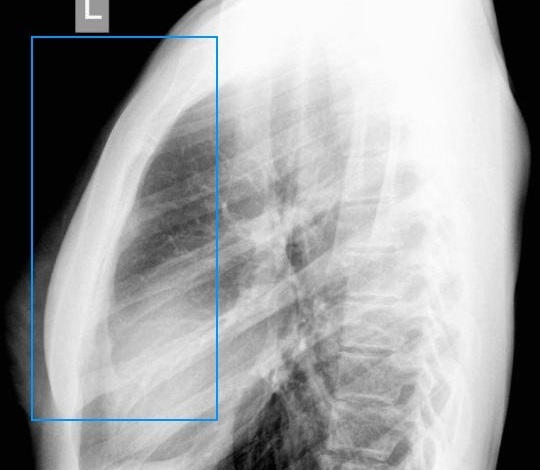

Воспалительные процессы дыхательной системы

Боль в области грудной клетки может быть вызвана заболеваниями органов дыхания, такими как пневмония, бронхит, туберкулез или новообразования. Чтобы различить легочные заболевания, важно учитывать сопутствующие симптомы: кашель, общую слабость, повышенную потливость и температуру тела.

При появлении дискомфорта или болей в груди необходимо немедленно обратиться к врачу. Специалист соберет анамнез и проведет осмотр, после чего назначит диагностические процедуры, такие как УЗИ, МРТ, рентгенография и анализы крови, в зависимости от ситуации.